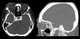

A carotid-cavernous fistula results from an abnormal communication between the arterial and venous systems within the cavernous sinus in the skull. It is a type of arteriovenous fistula. [Source: Wikipedia ]